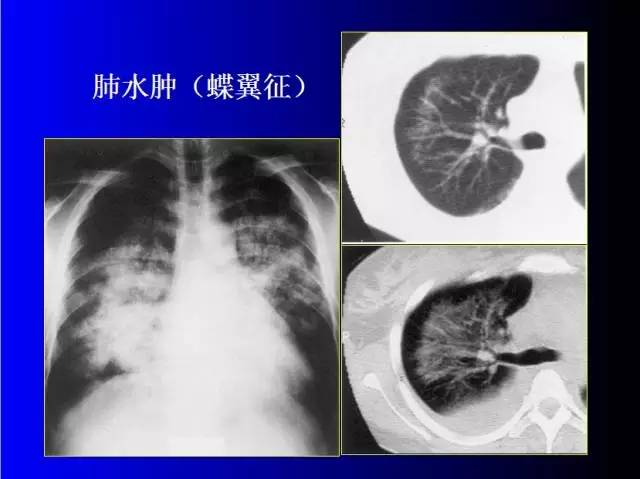

肺部基础X片及CT片解读